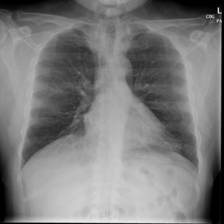

To pre-train a high-performance X-ray foundation model, the first thing we need to do is the collection of large-scale X-ray images. Therefore, a large-scale and high-resolution dataset that contains X-ray medical images is collected for the pre-training. Some representative samples are visualized in Fig. 3.